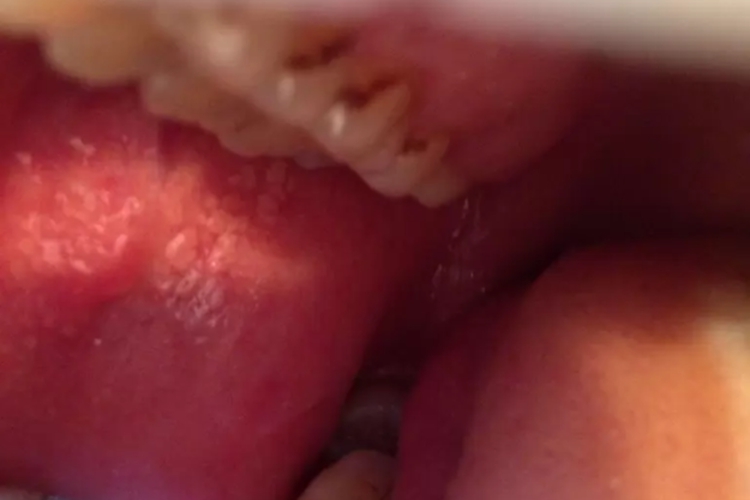

迷脂症又称皮脂腺异位症,疾病表现为黏膜或皮肤黏膜交界处淡黄色针尖大的斑疹或丘疹、皮疹稀疏分布或相互融合。根据受累部位不同分为口唇部位、颊黏膜。皮损发展到一定程度后静止,患者亦无不良感觉。